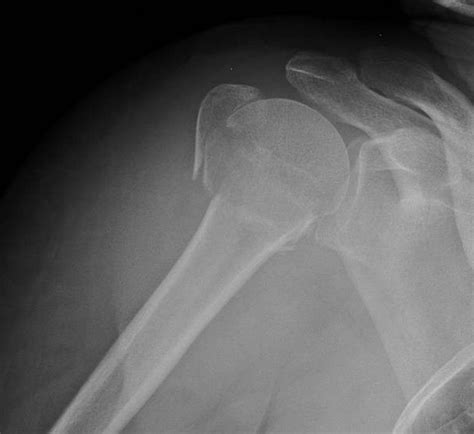

Classification of Proximal Humerus Fractures

Proximal humerus fractures are classified based on the location and pattern of the fracture. The most common classification systems include:

• Neer Classification: This system categorizes fractures based on the number of parts involved (one, two, three, or four parts).

• AO/OTA Classification: This system uses a more detailed coding system to describe the fracture pattern and severity.

Understanding the classification of the fracture helps healthcare providers determine the appropriate treatment plan.